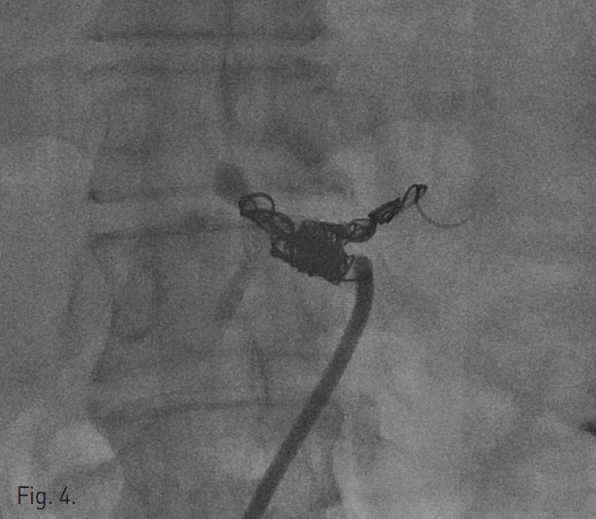

조영증강 복부 CT에서 잔류위의 점막부 조영증강이 일부 끊어져 있는 소견이 보였고, 그 주변으로 혈종과 액체저류 소견이 보여 잔류위 봉합부의 열개(dehiscence)가 있는 것으로 생각된다(Fig. 1a). 액체저류는 주변으로 파급되어 췌장을 둘러싸고 퍼지는 양상이며 비장동맥 주위까지 침윤되어 있었다. 비장동맥의 근위부가 약간 불규칙하게 보였으나 급성 출혈이나 가성동맥류 소견은 뚜렷하지 않았다(Fig. 1b).

Fig. 1

A. Contrast-enhanced CT scan shows focal dehiscence in the residual stomach wall (arrow) with surrounding fluid collection.